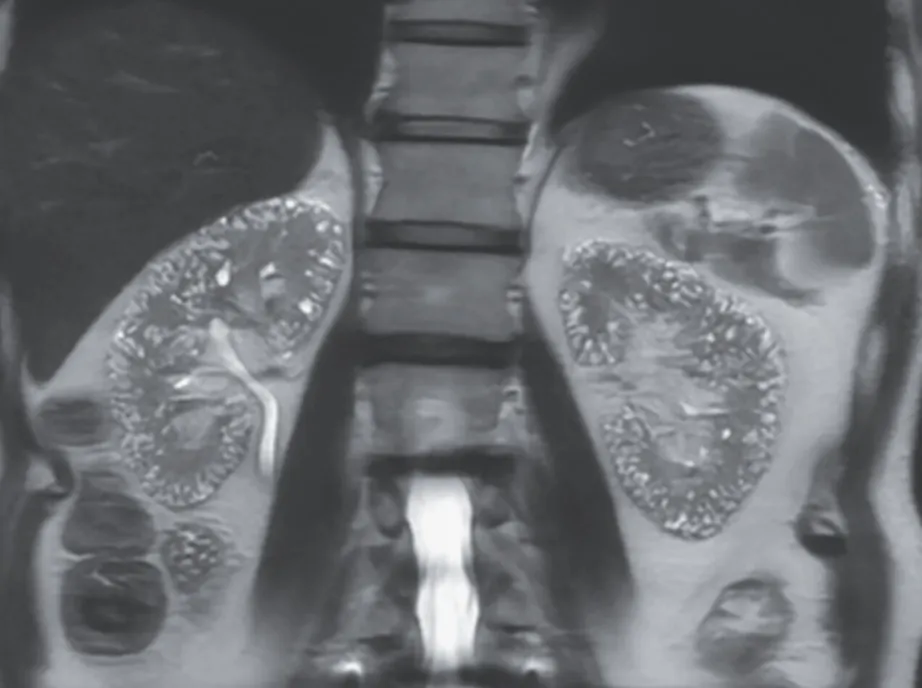

Na investigação de quadro de lesões de pele e calcificação extra-esquelética, observou-se um tumor calcificado no átrio esquerdo, bem como lesões ateroscleróticas calcificadas na aorta, artérias ilíacas e femorais, além de depósitos de cálcio no tecido subcutâneo e lesões na pele (figura abaixo).